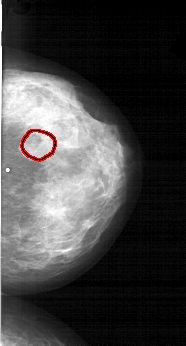

A_1566_1.RIGHT_CC

RIGHT_CC LINES 5866 PIXELS_PER_LINE 3151 BITS_PER_PIXEL 12 RESOLUTION 43.5 OVERLAY

FILE: A_1566_1.RIGHT_CC.OVERLAY

TOTAL_ABNORMALITIES 1

ABNORMALITY 1

LESION_TYPE MASS SHAPE LOBULATED MARGINS OBSCURED

ASSESSMENT 4

SUBTLETY 3

PATHOLOGY BENIGN

TOTAL_OUTLINES 1

BOUNDARY